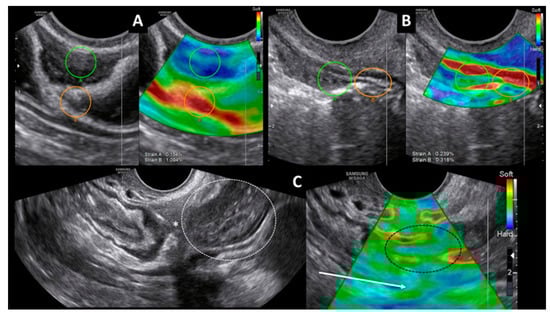

Transvaginal Strain Elastosonography May Help in the Differential Diagnosis of Endometriosis?

- Szabó, G.; Madár, I.; Bokor, A.; Brubel, R.; Csibi, N.; Rigó, J., Jr. Preoperative mapping of deep infiltrating endometriosis in the posterior compartment using transvaginal strain elastography and IDEA classification. Ultrasound Obst. Gyn. 2019, 54 (Suppl. 1), 50. [Google Scholar] [CrossRef]